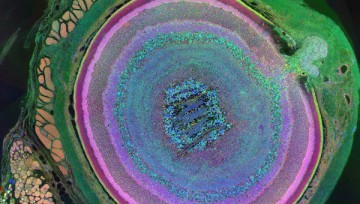

Парадокс стволовых клеток

Сергей Львович Киселев – профессор, доктор биологических наук, научный руководитель отдела эпигенетики, главный научный сотрудник Института общей генетики имени Вавилова РАН.